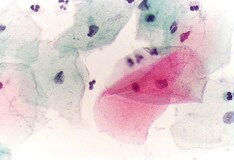

The approval was based primarily on data from a clinical study of more than 18,000 women aged 15 through 25 years, showing that the vaccine was 93% effective for preventing cervical precancer (cervical epithelial neoplasia grade ≥ 2 lesions and adenocarcinoma in situ) and cancer associated with HPV types 16 and 18, which are responsible for approximately 75% of cervical cancers in North America.

Use of the vaccine was also shown to prevent 70% of precancerous lesions, regardless of HPV type; further analysis revealed an approximately 89% efficacy rate against lesions caused by HPV type 31, the third most common cancer-causing type in North America.

Because no vaccine is 100% effective and vaccination does not protect against previously acquired HPV infection or infection with types not included in the vaccine, regular Papanicolaou tests should still be used to detect precancerous lesions for treatment.